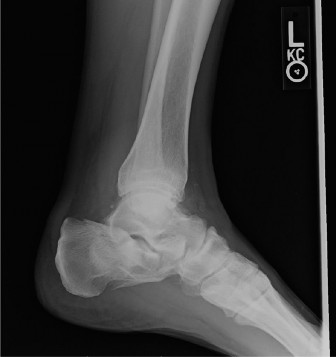

CASE 34 You see a 14-year-old girl in your clinic for the first time who has a …